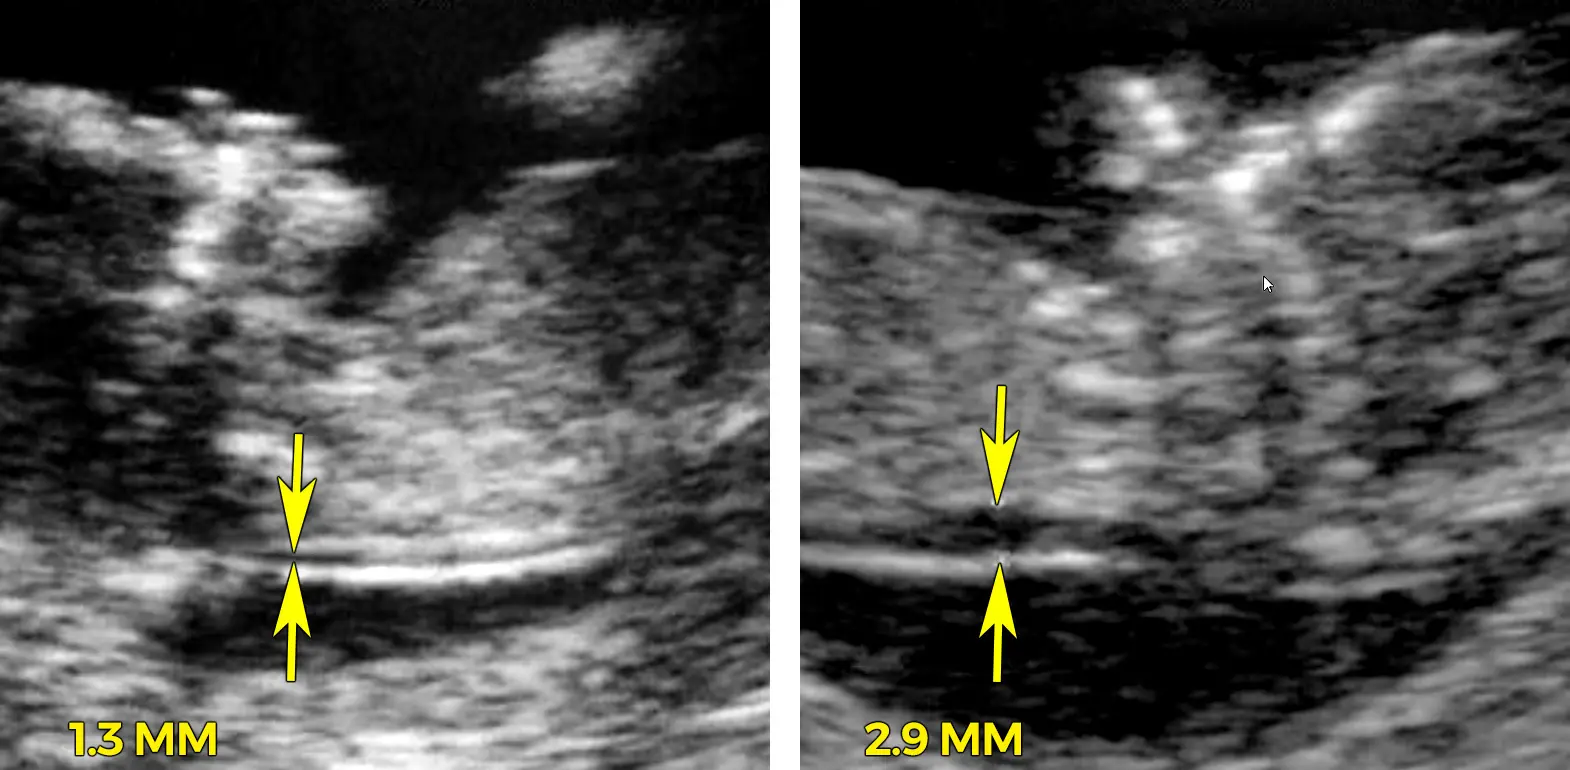

Die Nackenfaltenmessung wird im Rahmen eines Ultraschalluntersuchs durchgeführt. Der Arzt oder die Ärztin misst mit einem speziellen Gerät die Dicke der Nackenfalte des Fötus. Die Messung erfolgt in Millimetern und wird in einem Messprotokoll festgehalten. Die Nackenfalte ist eine Flüssigkeitansammlung im Nackenbereich des Fötus, die im ersten Trimester der Schwangerschaft normal vorhanden ist. Bei einem erhöhten Risiko für Chromosomenstörungen ist die Nackenfalte jedoch oft dicker als normal.

Neben der Nackenfalte werden bei der Nackenfaltenmessung auch andere Ultraschallmarker beurteilt, wie zum Beispiel die Länge des Nasenbeins und die Blutflussgeschwindigkeit in bestimmten Gefäßen des Fötus. Diese Marker können ebenfalls Hinweise auf mögliche Chromosomenstörungen geben.